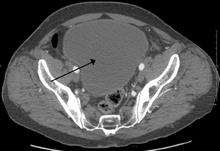

As seen on axial CT

Analysis of urine flow may aid in establishing the type of micturition (urination) abnormality. Common findings, determined by ultrasound of the bladder, include a slow rate of flow, intermittent flow, and a large amount of urine retained in the bladder after urination. A normal test result should be 20-25 mL/s peak flow rate. A post-void residual urine greater than 50 ml is a significant amount of urine and increases the potential for recurring urinary tract infections. In adults older than 60 years, 50-100 ml of residual urine may remain after each voiding because of the decreased contractility of the detrusor muscle. In chronic retention, ultrasound of the bladder may show massive increase in bladder capacity (normal capacity is 400-600 ml).